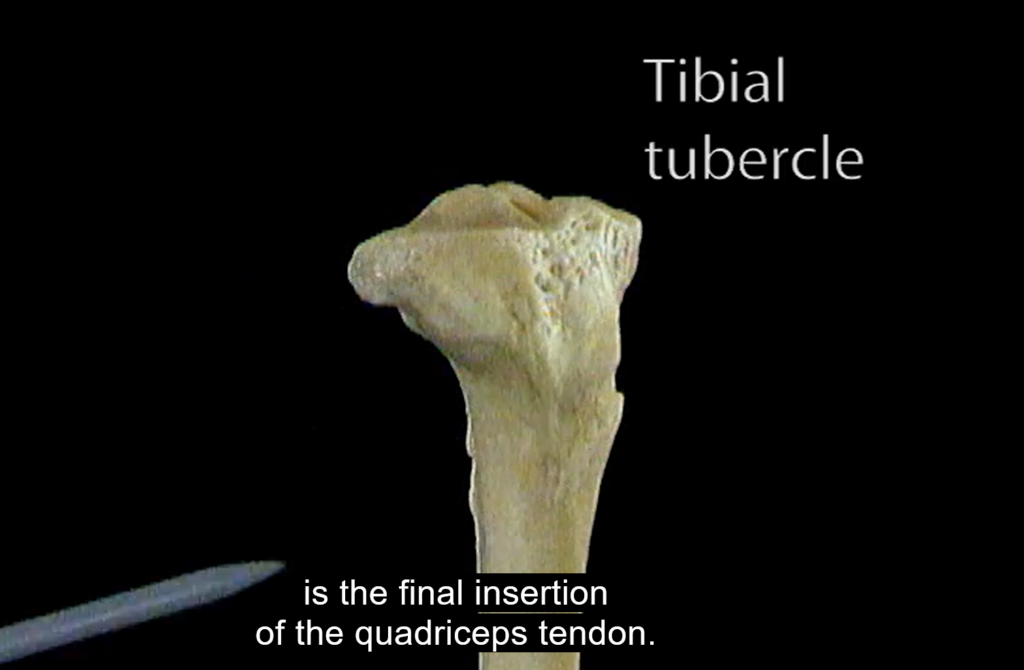

Dwa nowoczesne narzędzia online – Interaktywny Atlas Histologiczny oraz Wirtualny Atlas Anatomii Człowieka (Acland’s Video Atlas of Human Anatomy) – oferują bazę wysokiej jakości obrazów statycznych oraz materiałów wideo do nauki i zrozumienia mikroskopowych oraz makroskopowych struktur ludzkiego ciała.

Materiały Wirtualnego Atlasu Anatomii Człowieka (Acland’s Video Atlas of Human Anatomy) pokazują rzeczywiste tkanki i narządy w trójwymiarowej przestrzeni.

Kolekcję filmów można przeszukiwać według kategorii odpowiadającej anatomicznym częściom ciała oraz według alfabetycznie ułożonej listy nazw narządów i układów:

- kończyna dolna: biodro, kolano, podudzie i kostka, stopa;

Źródło zdjęć: Ackland’s Video Atlas of Human Anatomy; Interaktywny Atlas Histologiczny